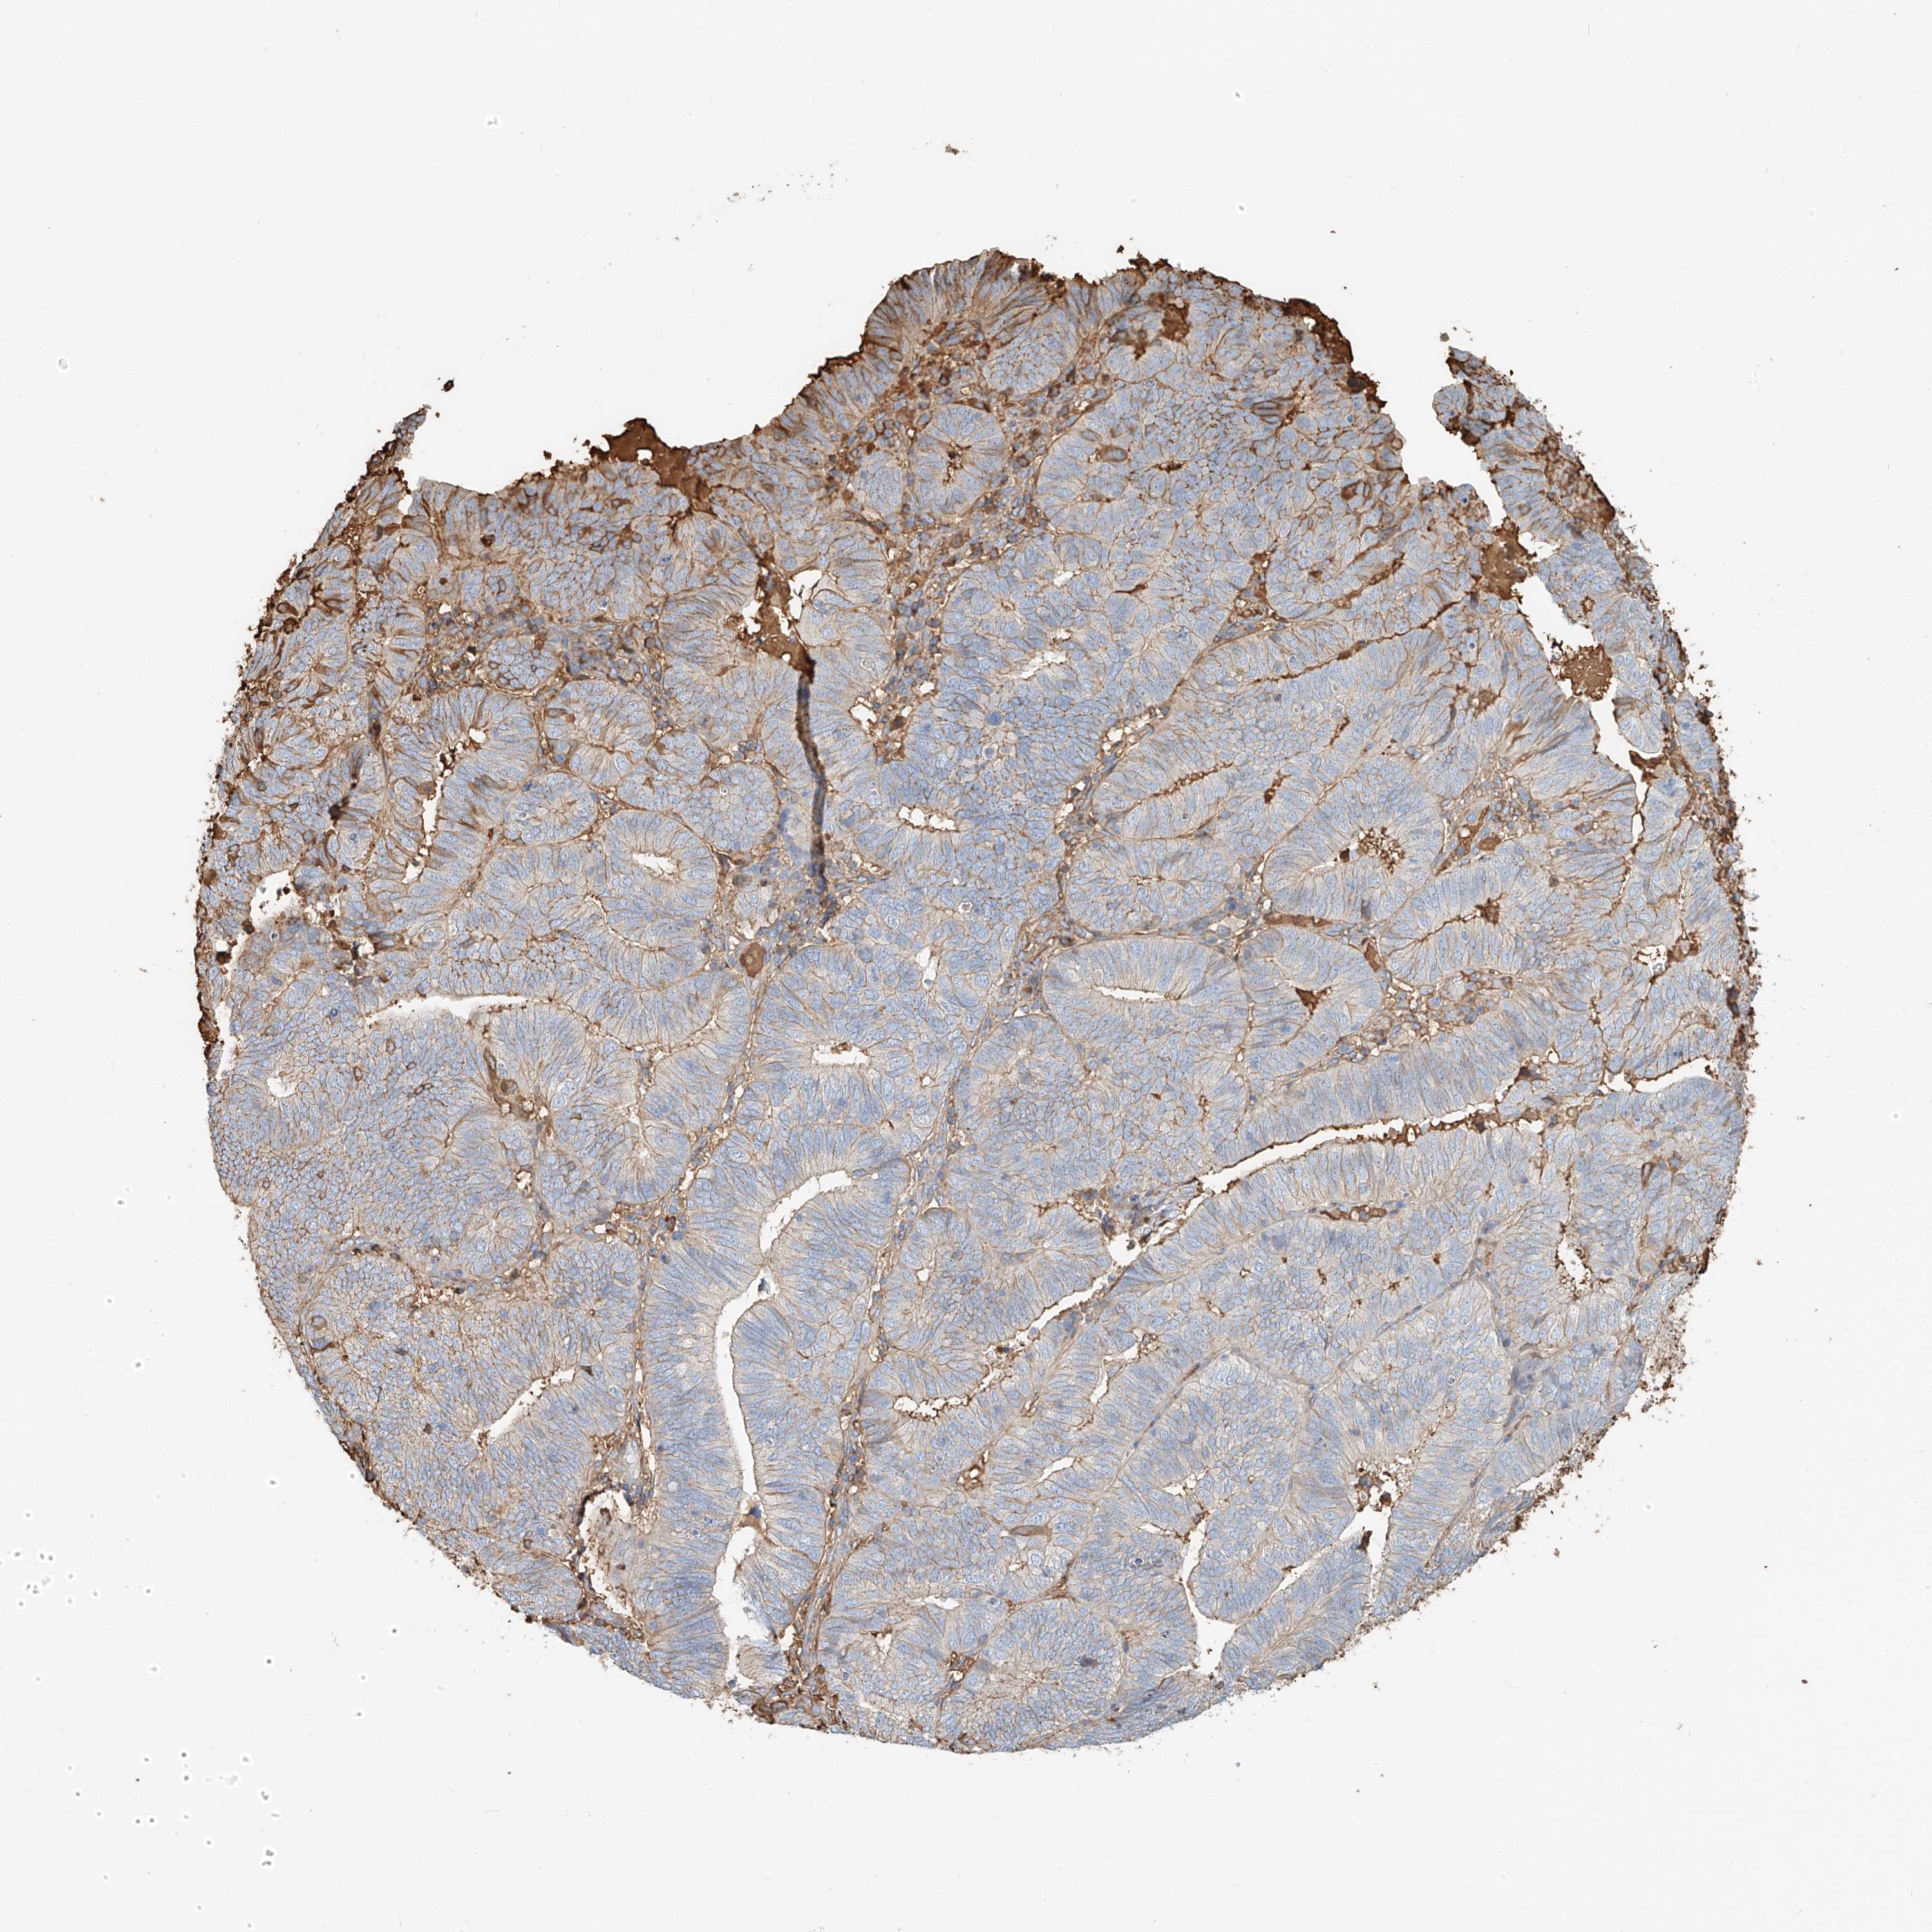

ENDOMETRIAL CANCER - Protein expressioni

A mouse-over function shows sample information and annotation data. Click on an image to view it in a full screen mode. Samples can be filtered based on level of antibody staining by selecting one or several of the following categories: high, medium, low and not detected. The assay and annotation is described here.

Note that samples used for immunohistochemistry by the Human Protein Atlas do not correspond to samples in the TCGA dataset.

Antibody stainingi

Antibody staining in the annotated cell types in the current human tissue is reported as not detected, low, medium, or high, based on conventional immunohistochemistry profiling in selected tissues. This score is based on the combination of the staining intensity and fraction of stained cells.

Each image is clickable and will lead to virtual microscopy that enables deeper exploration of all samples and also displays staining intensity scores, fraction scores and subcellular localization as well as patient and tissue information for each sample.

Antibody HPA030606

Staining

High

Medium

Low

Not detected

Intensity

Strong

Moderate

Weak

Negative

Quantity

>75%

75%-25%

<25%

None

Location

Nuclear

Cytoplasmic/membranous

Cytoplasmic/membranous,nuclear

Adenocarcinoma, NOS